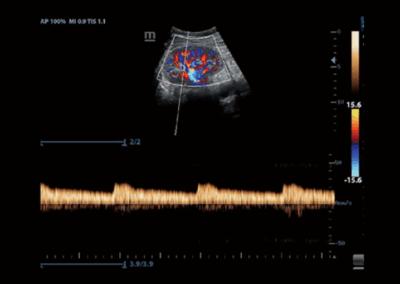

Z50

Sistema de diagnóstico ecográfico.

Con la combinación definitiva de alto rendimiento, aplicaciones clínicas integrales y diseño integrado, el Z50 lo ayudará a responder de manera más rápida y eficaz. El cambio de un sistema en blanco y negro a un sistema Doppler a color altamente eficiente ahora se ha vuelto más fácil y simple que nunca, lo que hace posible ir más allá de los límites y trascender lo habitual cuando se trata de la atención de los pacientes.